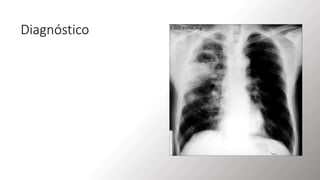

Diagnóstico

• Evaluación de los factores de riesgo.

• Manifestaciones clínicas.

• Imagenología de tórax: Radiografía de tórax y

TAC.

• La radiografía de tórax constituye el pilar

fundamental con el hallazgo típico de una

cavidad con nivel hidroaéreo en una

localización característica; suele ser el

segmento posterior del lóbulo superior, o el

superior del lóbulo inferior, siendo más

frecuente en el pulmón derecho.

RX DE TORAX

• Radiografía de tórax (vista PA) de un paciente con

absceso pulmonar

• Una cavidad grande de paredes gruesas

(superposición verde) en la región perihiliar del

pulmón derecho contiene un nivel hidroaéreo

(indicado por una línea roja).

• El diferencial de esta apariencia incluye abscesos

(bacterianos, micobacterianos, micóticos),

granuloma cavitario no infeccioso y lesión maligna

cavitaria.